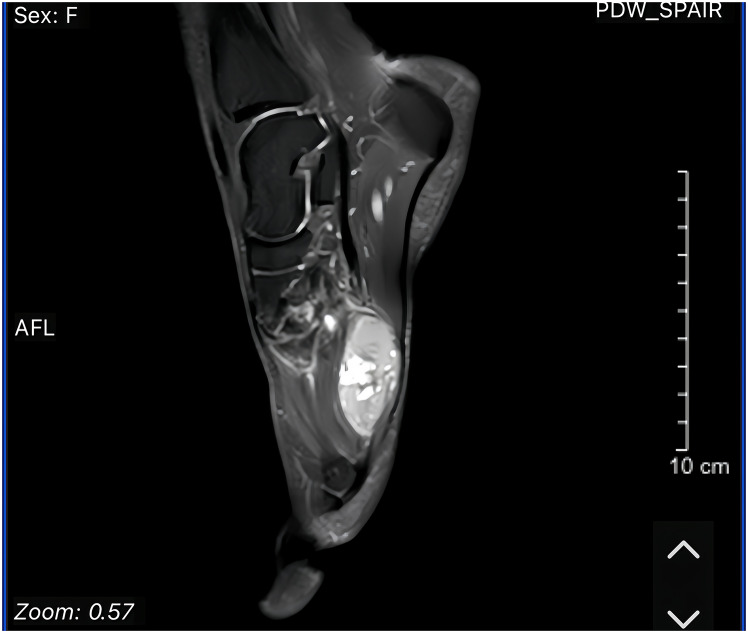

Case presentation: The tumor presented as a well-circumscribed mass. Following complete excision, no recurrence was observed at the six-month follow-up. Histological examination revealed tumor cells exhibiting mild nuclear atypia and very low mitotic activity. Immunohistochemical analysis showed diffuse positive staining for S100, glial fibrillary acidic protein (GFAP), and CD56, variable expression of smooth muscle actin, and negative staining for SOX10 and P63. Targeted RNA sequencing identified RREB1 (exon 8)-MRTFB (exon 11) fusion transcripts. Collectively, these findings suggest the possibility of a previously unreported extralingual ECT involving the plantar fascia. However, its atypical morphology and uncommon anatomical location posed significant diagnostic challenges.